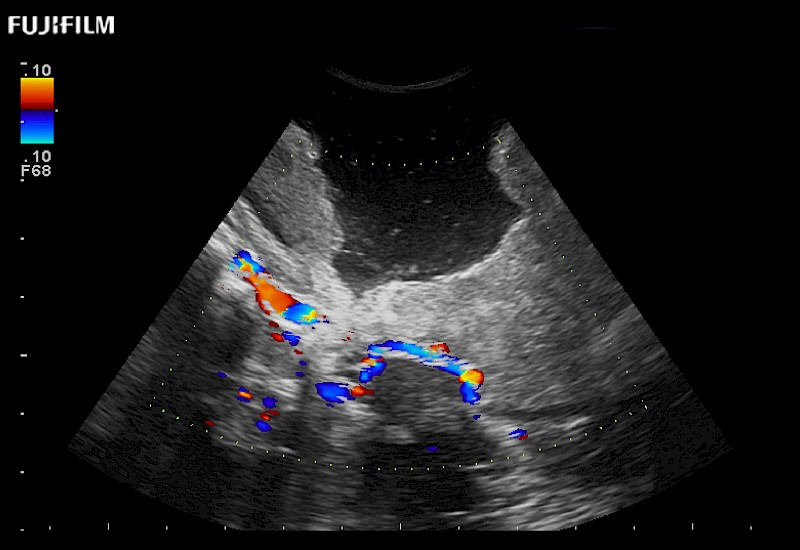

Exclusive 10mm side‐fire linear array transducer with 2.87mm diameter is ideal for real‐time visualization through and behind structures and instant, scalable definition of anatomy and vascularity including the ability to delineate and define tumor margins.

Guidance is the fundamental purpose for all of our surgical ultrasound technology. Fujifilm Healthcare is committed to designing tools that help neurosurgeons navigate inside the human body and provide the necessary information to immediately make critical surgical decisions.